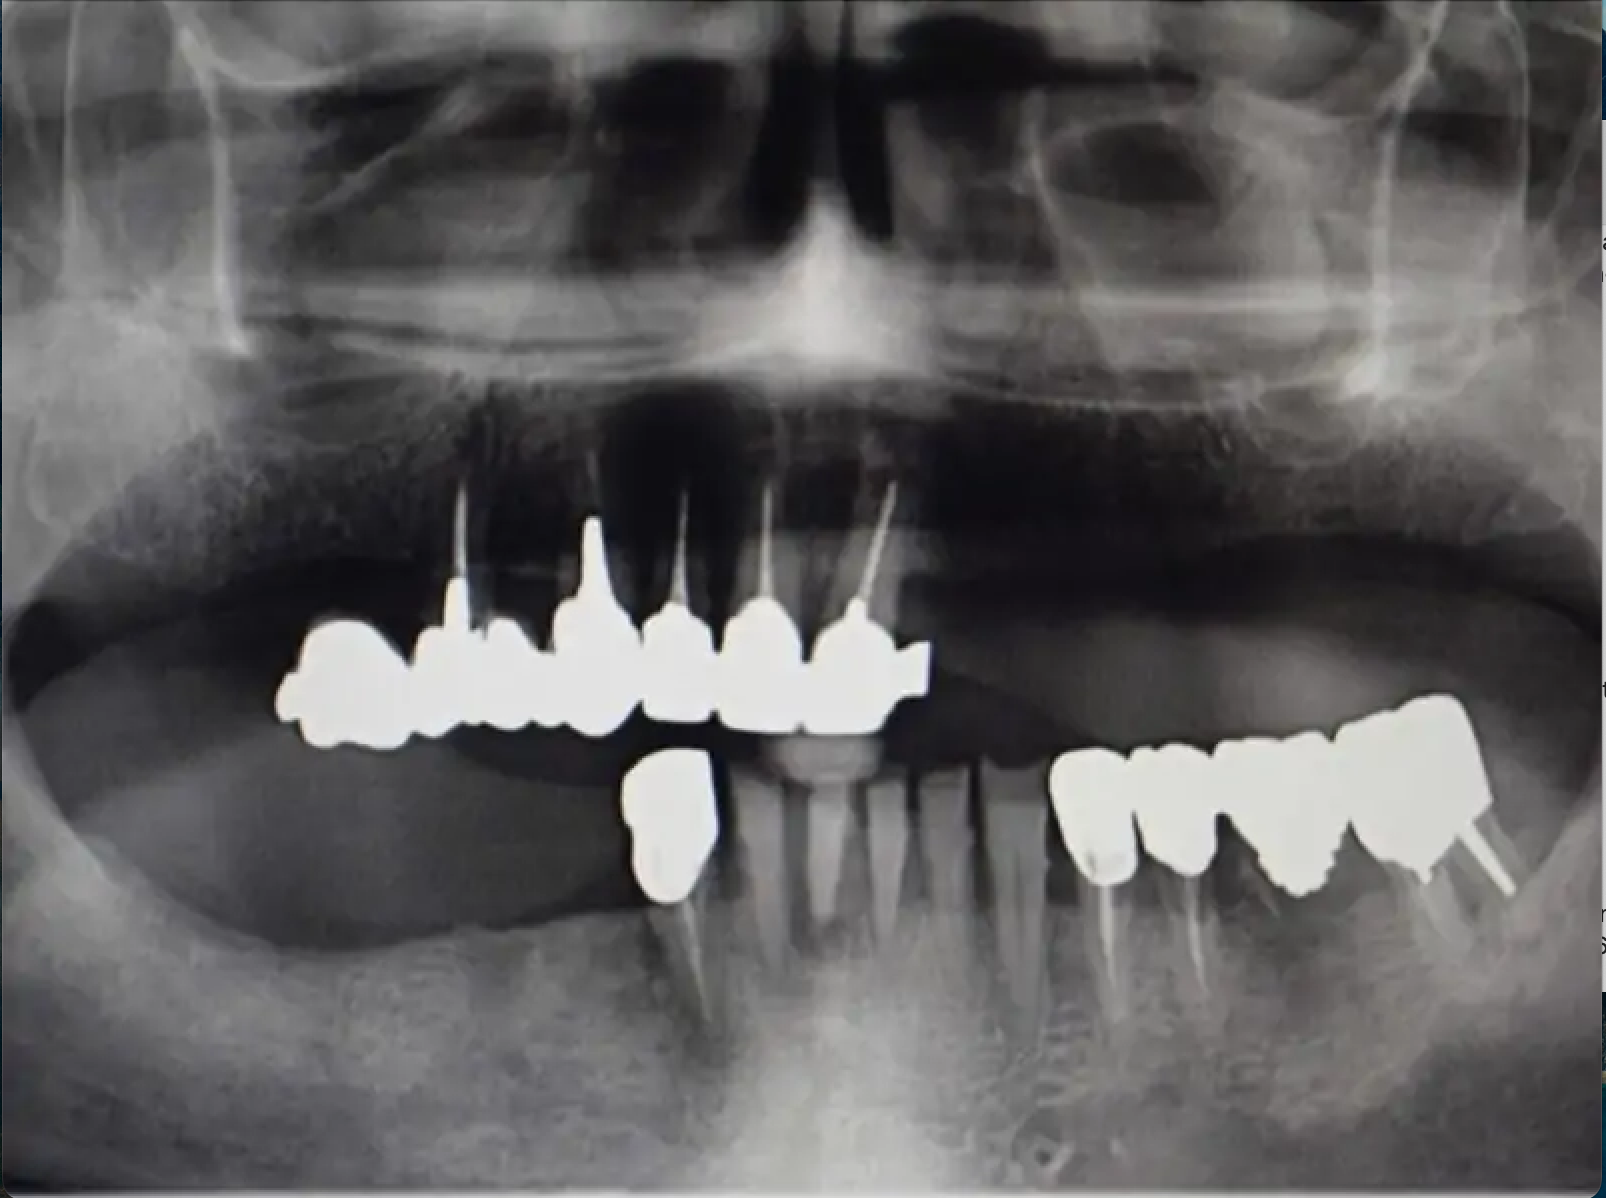

Чтобы минимизировать травмирование тканей, установили имплантаты безлоскутным методом, используя стопоры для точного определения длины препарирования. Сразу после операции у пациента остались заживляющие винты на имплантате и его предыдущий протез, в котором мы сделали полость внутри, чтобы избежать травмирования имплантатов. Через 5 месяцев пациент вернулся. Мы сняли слепок и изготовили дубликат протеза, который затем использовали для изготовления балки, фиксируемой поверх монокулярных альвеолярных протезов (MUA), а также внутреннего каркаса и ретенционных колпачков.

Шаблон позволяет легко определить наклон препарирующих инструментов, а также выбрать угловой монокулярный альвеолярный протез (MUA). Во время второго сеанса мы просто установили абатменты Multi unit и зафиксировали балку протеза соответствующими винтами, прежде чем примерить и проверить окклюзию постоянного протеза.